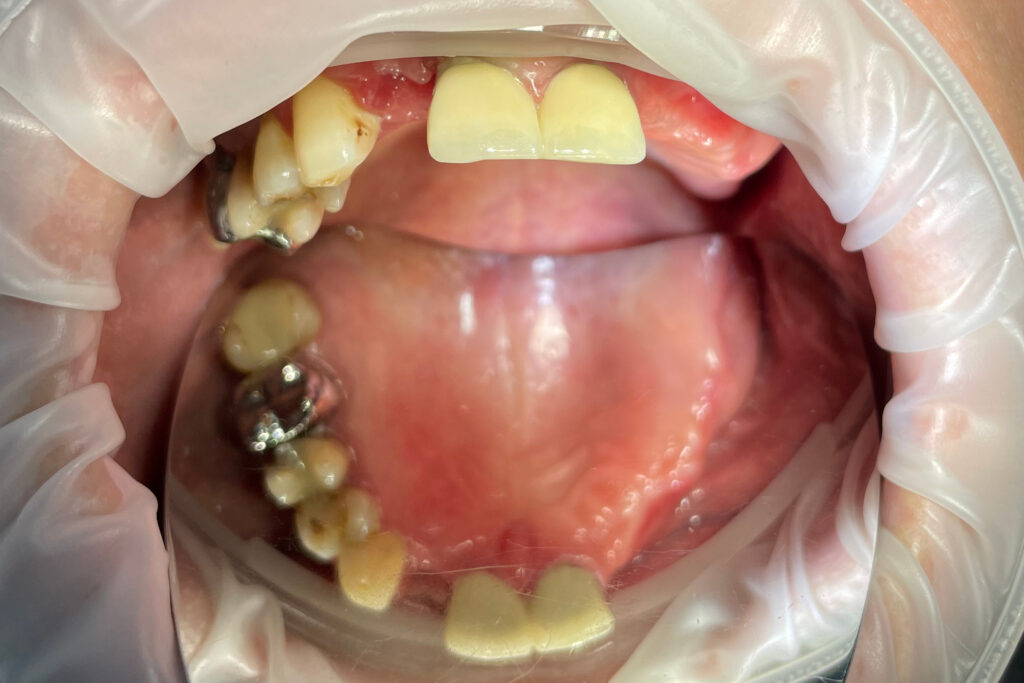

Ситуация до лечения

Жалобы: Пациент обратился к нам с целью проведения комплексной имплантации верхней челюсти.

Диагноз: Частичная вторичная адентия верхней челюсти.

пациент до протезирования